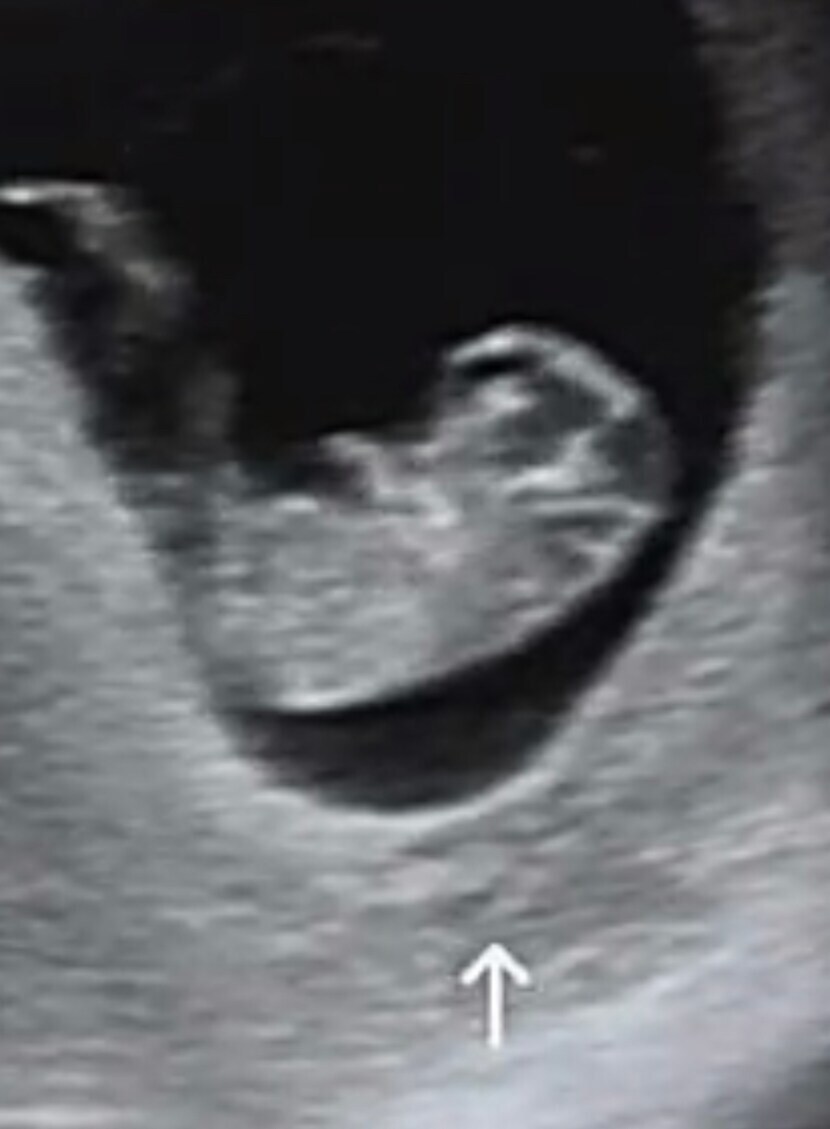

λ μ¬κΈ° μμ΄μ~

νκ³ μ μ‘°κ·Έλ§ μμ μ΄μ°λ νλ€μ΄μ£Όλμ§μπ